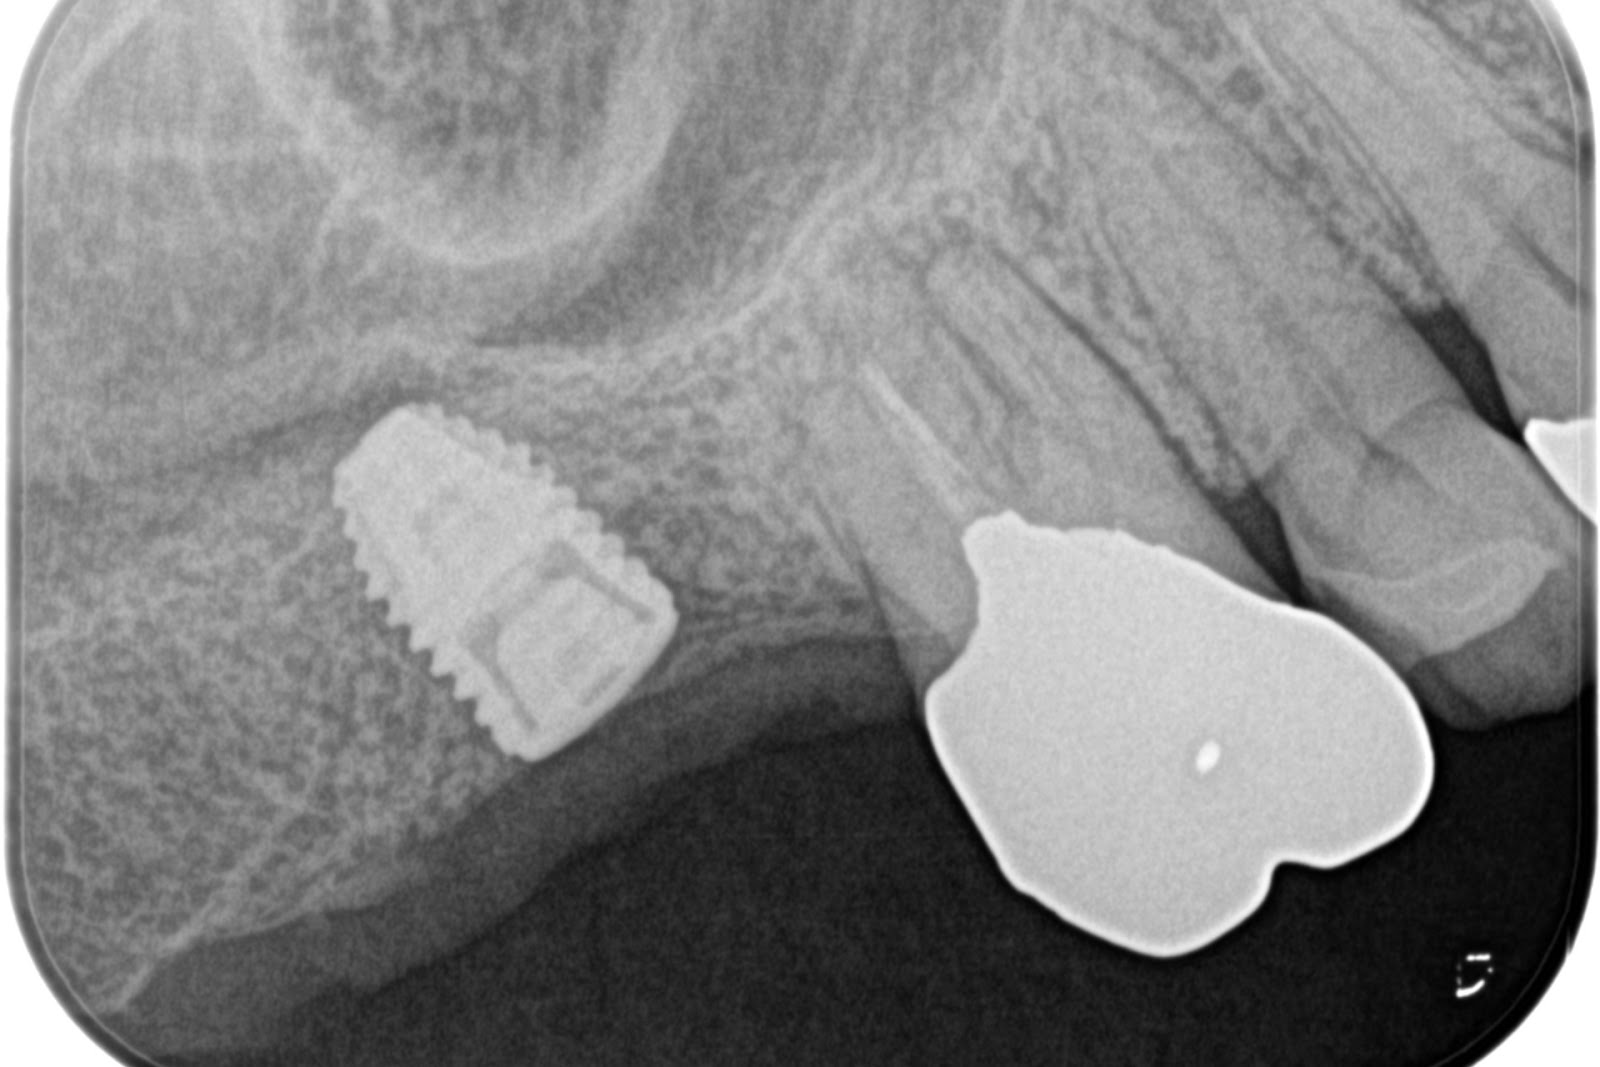

手術後(右上)

上部構造セット後(右上)